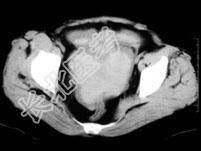

- 单项选择题女,32岁, 因停经46天,少许不规则阴道流血15天, 下腹胀痛3天入院,后穹窿穿刺抽出不凝血, CT检查如图所示,下列说法错误的是 ( )

A、在左附件区可见一椭圆形略高密度病灶

B、病灶外缘较光整

C、盆腔内较高密度积液

D、考虑为宫外孕

E、考虑为卵巢巧克力囊肿